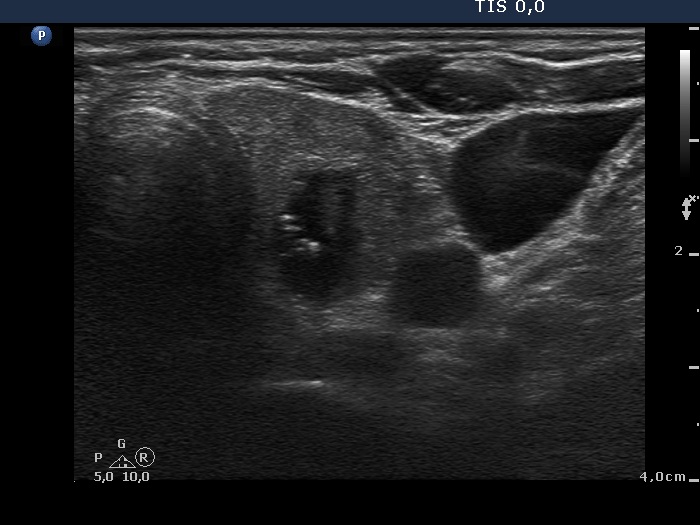

Ultrasonography: the thyroids were moderately hypoechogenic and contained several discrete, circumscribed lesions. There was a hyperechogenic nodule in the lower part of the right lobe while a cystic nodule in the upper part of the left lobe.

The thyroid is hypoechogenic and is surrounded with a relatively thin echonormal rim. This makes an appearance if both lobes were composed of a large hypoechogenic nodule. However, the echonormal rim corresponds to thickened connective tissue; a frequent phenomenon in an operated thyroid.

The upper part of the right lobe seems to be nodular, i.e. composed of two nodules at first sight. However, an insertion of the connective tissue and an acoustic shadow of a coarse calcification divides this part of the thyroid to two lesions. These do not fit nodules in a pathological sense.